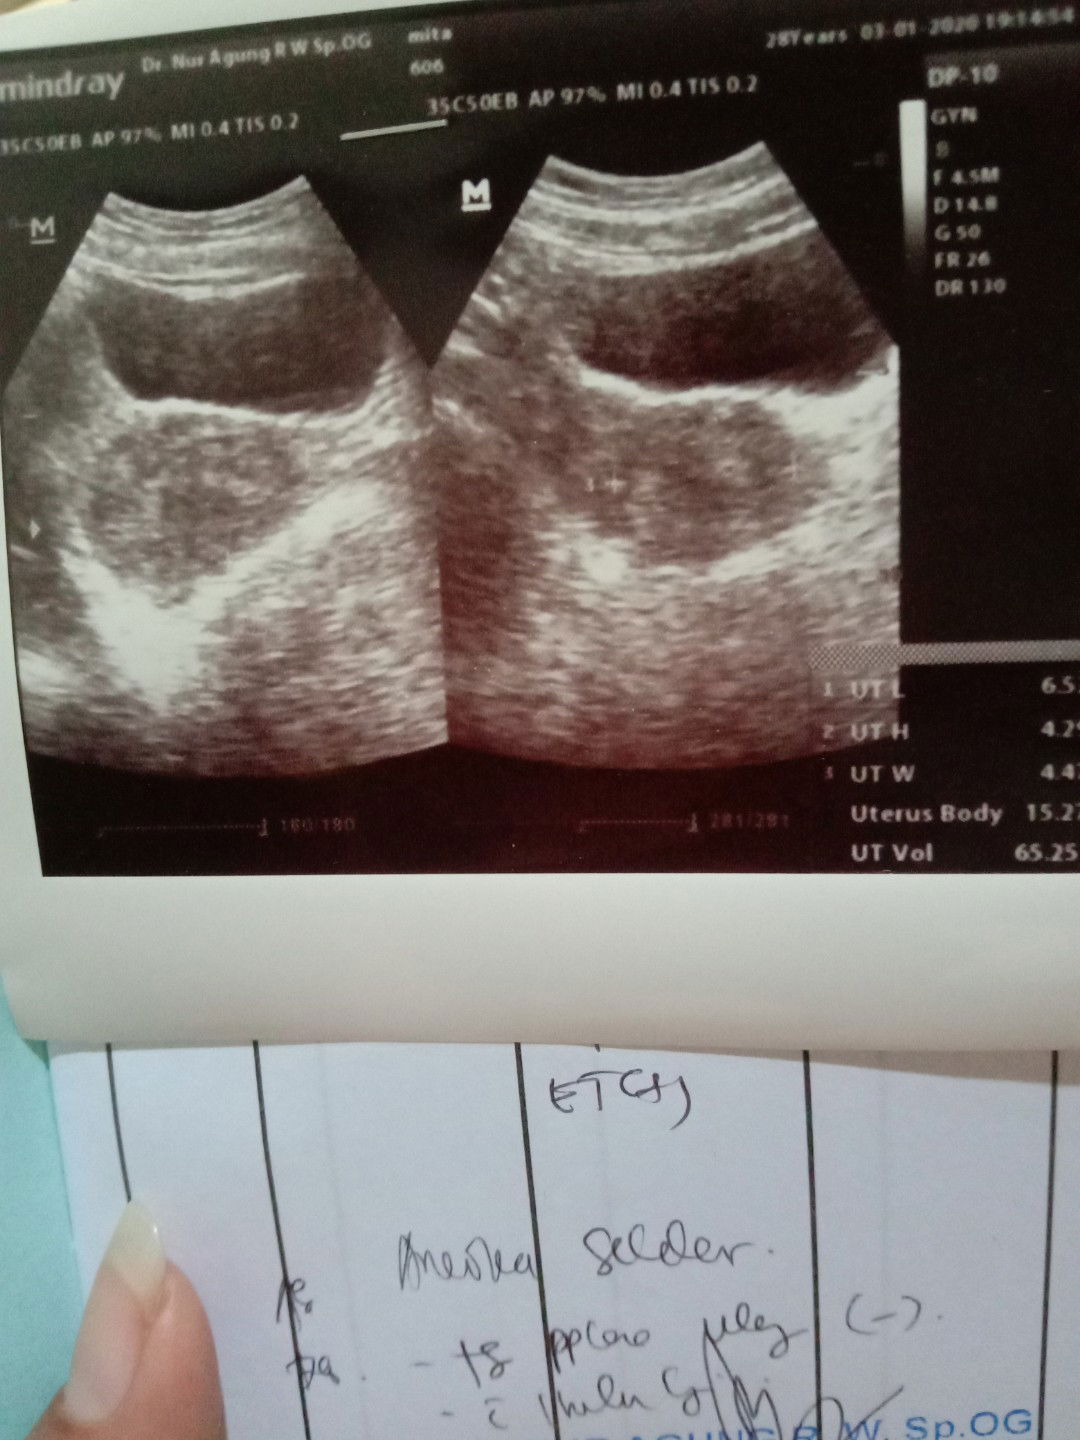

Ini gimana baca hasil USG nya y bund..